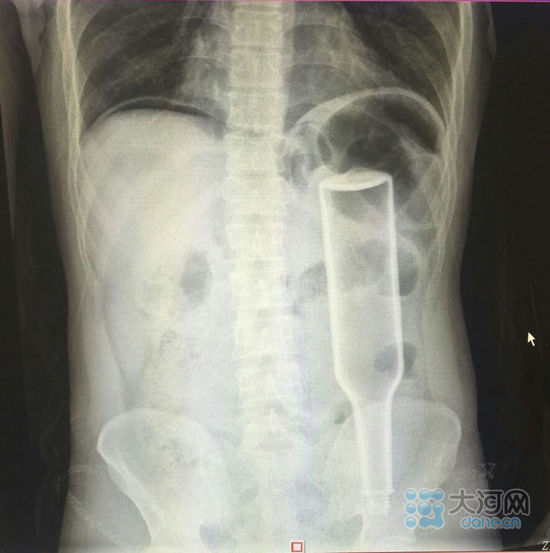

ݐݒeIçIbzYĔH_Y,ĕղAnҡuI,vNR18gYVUoĒɕsYd,LDnΒҹL,F飤,Uo\MW},ko夣ɒ,_YѴHպb˥|,ͭ˓ptɤ,}Ig||